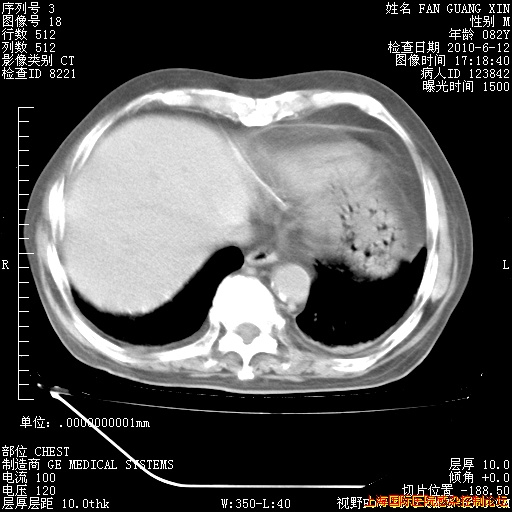

今天复查CT

今天CT

整整相隔30天的肺部CT好像有所好转啊。甲强龙减量第3天,需要观察体温。

海管,自昨日你和我通完话后,不知您岳父消化道症状有无缓解?体温怎样?阅读7.12日胸部ct,个人认为目前激素治疗是有效的,甲强龙减量是适宜的。因在抗痨治疗,需密切观察肝功、肾功能和血常规。不过,老年、长期住院和大量使用激素,很担心菌群失调发生